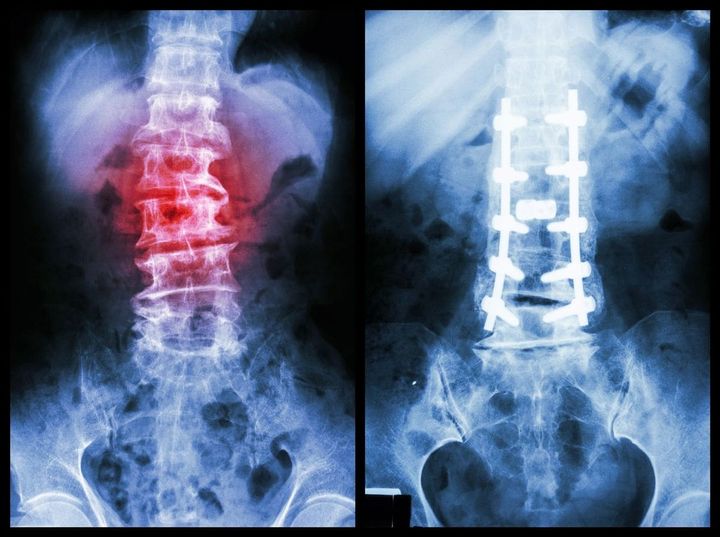

2012年の冬頃。77歳になっていた母親は、強い腰痛が続いていた。烏丸さんが病院に行くように説得すると、腰椎圧迫骨折と診断された。幸い、1カ月程度の入院で済んだ。

脊椎の骨折と手術後固定されたレントゲン写真

※写真はイメージです

ところが、翌2013年の8月。母親は2度目の腰椎圧迫骨折に。今度は入院ではなく、自宅静養だった。